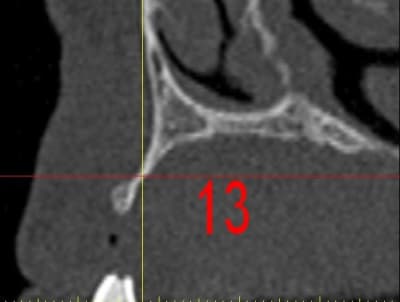

dar13_daauc7.jpg

La première diapo est un essai pour justifier le concept (os non destiné à une utilisation greffe)

la deuxième est "tapée" dans une tête de femur de mauvais qualité (rejetée)

la troisième et suivante ce sont "les greffons" définitifs.

Pour la mise en forme de la pièce 1 (appui 12) avec la mise en place, le choix de la tête de fémur, et les discussions pour expliquer la mise en forme, il a fallu 1 h environ, qui pourrait etre réduite à une trentaine de minutes, dans un cas comme celui ci, ce qui est déjà énorme pour l'os d'un patient (mise à nu ect...), sans parler des différents stress.